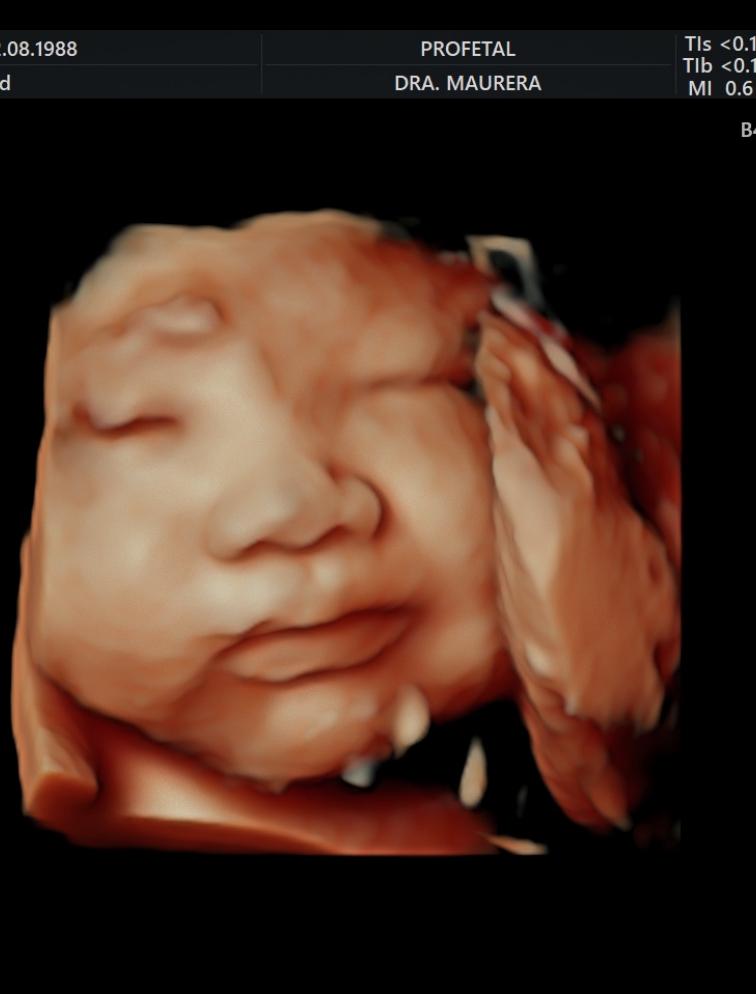

• Ecografía Morfológica Doppler (Semanas 16-26): Un estudio detallado de cada parte del cuerpo fetal (cerebro, corazón, columna, órganos y extremidades) para descartar anomalías estructurales.